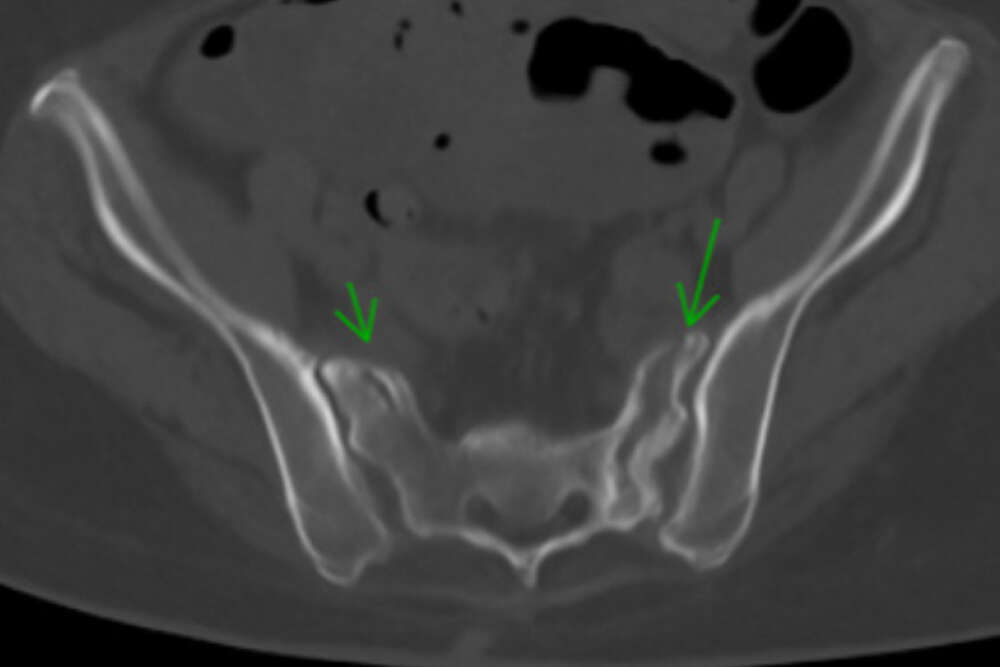

- A single iFuse TORQ TNT™ implant was placed in the S2 corridor, spanning the sacrum and crossing both SI joints, addressing the left sacral alar nonunion and providing pelvic ring stability (Figs. 2-4).

Cunningham 1c